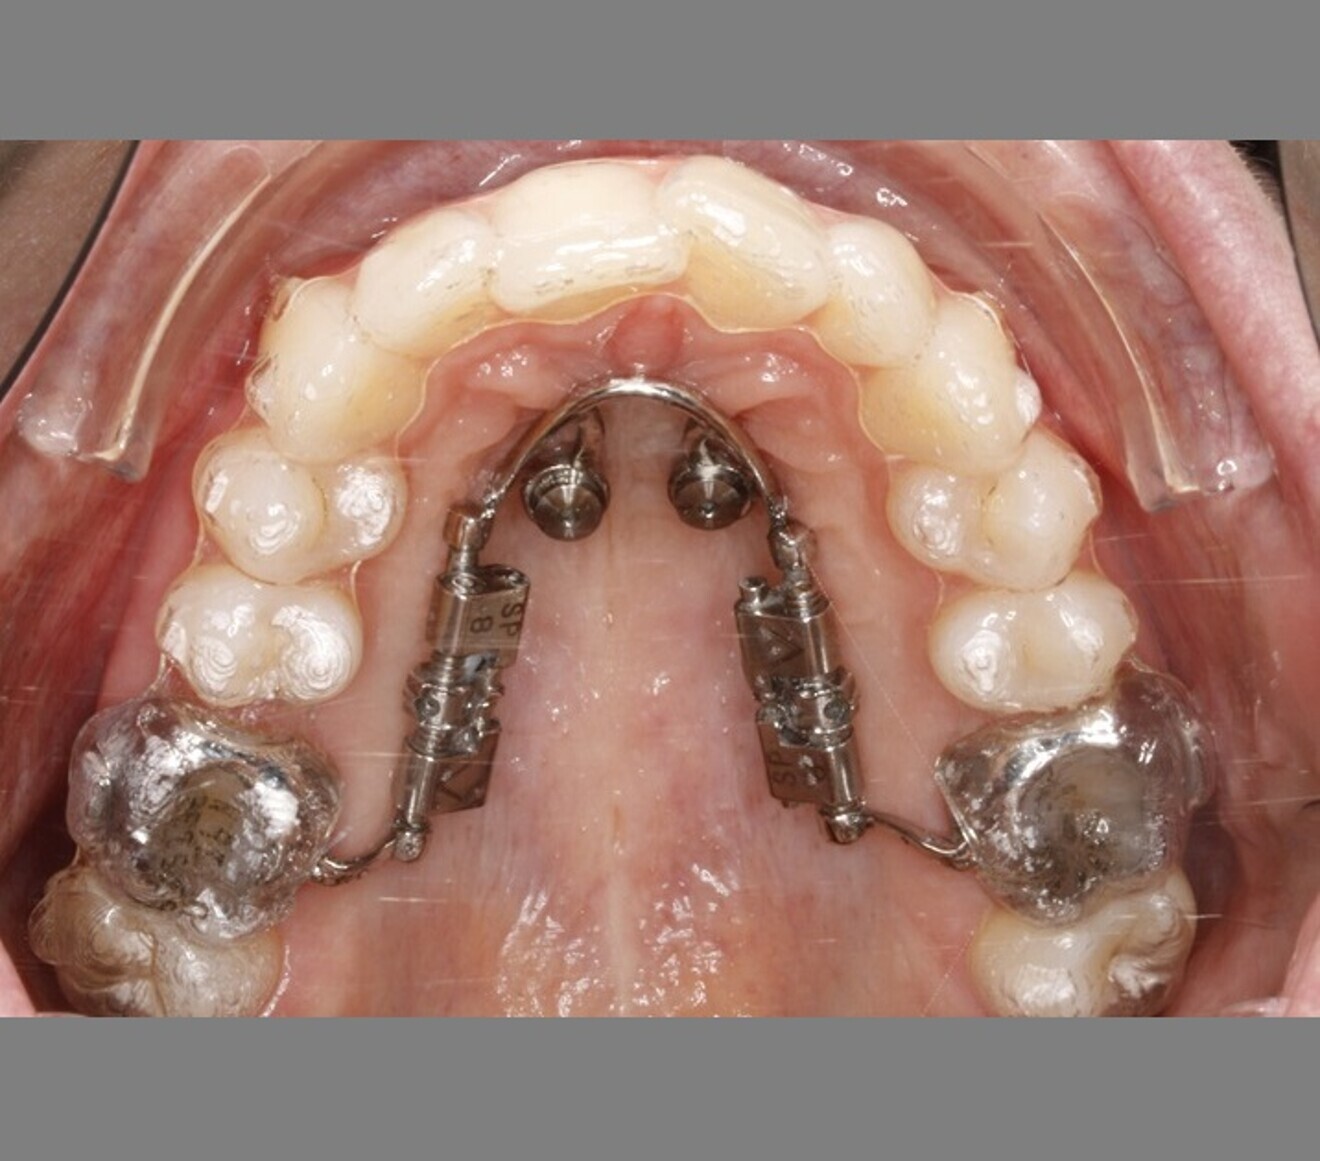

After an intra-oral scan, the positions of the mini-implants (BENEfit, 2 × 9 mm; PSM Medical) and of a bilateral distaliser were digitally planned. The distaliser (TADMAN) was manufactured using the selective laser melting process (Fig. 4). A simultaneously planned insertion guide (TADMAN) allowed for precise placement of the mini-implants and immediate fitting of the distaliser in a single appointment (Fig. 5).

Since a one-phase treatment approach was planned, an additional scan was taken immediately afterwards to produce the aligners (Invisalign, Align Technology). The goal was to achieve simultaneous bilateral molar distalisation and alignment of all the teeth using the aligners. To facilitate this, a distalisation rate of 0.2 mm per week was set, corresponding to a quarter turn of a screw with a thread pitch of 0.8 mm. The distalisation was planned asymmetrically because the molars in the maxillary right quadrant had drifted further mesially than those in the maxillary left quadrant (Fig. 6). The patient was given specific instructions on which aligner to activate the distaliser screws with. The distalisation was completed by the 20th aligner.

Fig. 4: Digital planning of the distaliser with metal attachments on the shells.

Fig. 5: Insertion guide.

Fig. 6: Skeletally anchored distaliser used simultaneously with aligners. Greater distalisation was performed in the maxillary right quadrant than in the maxillary left quadrant.